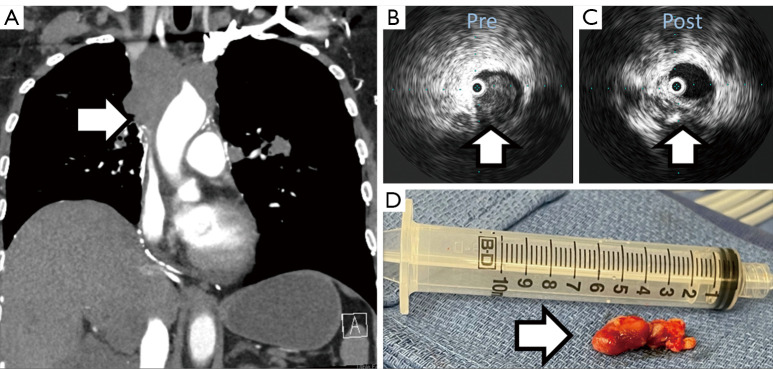

Abstract Image